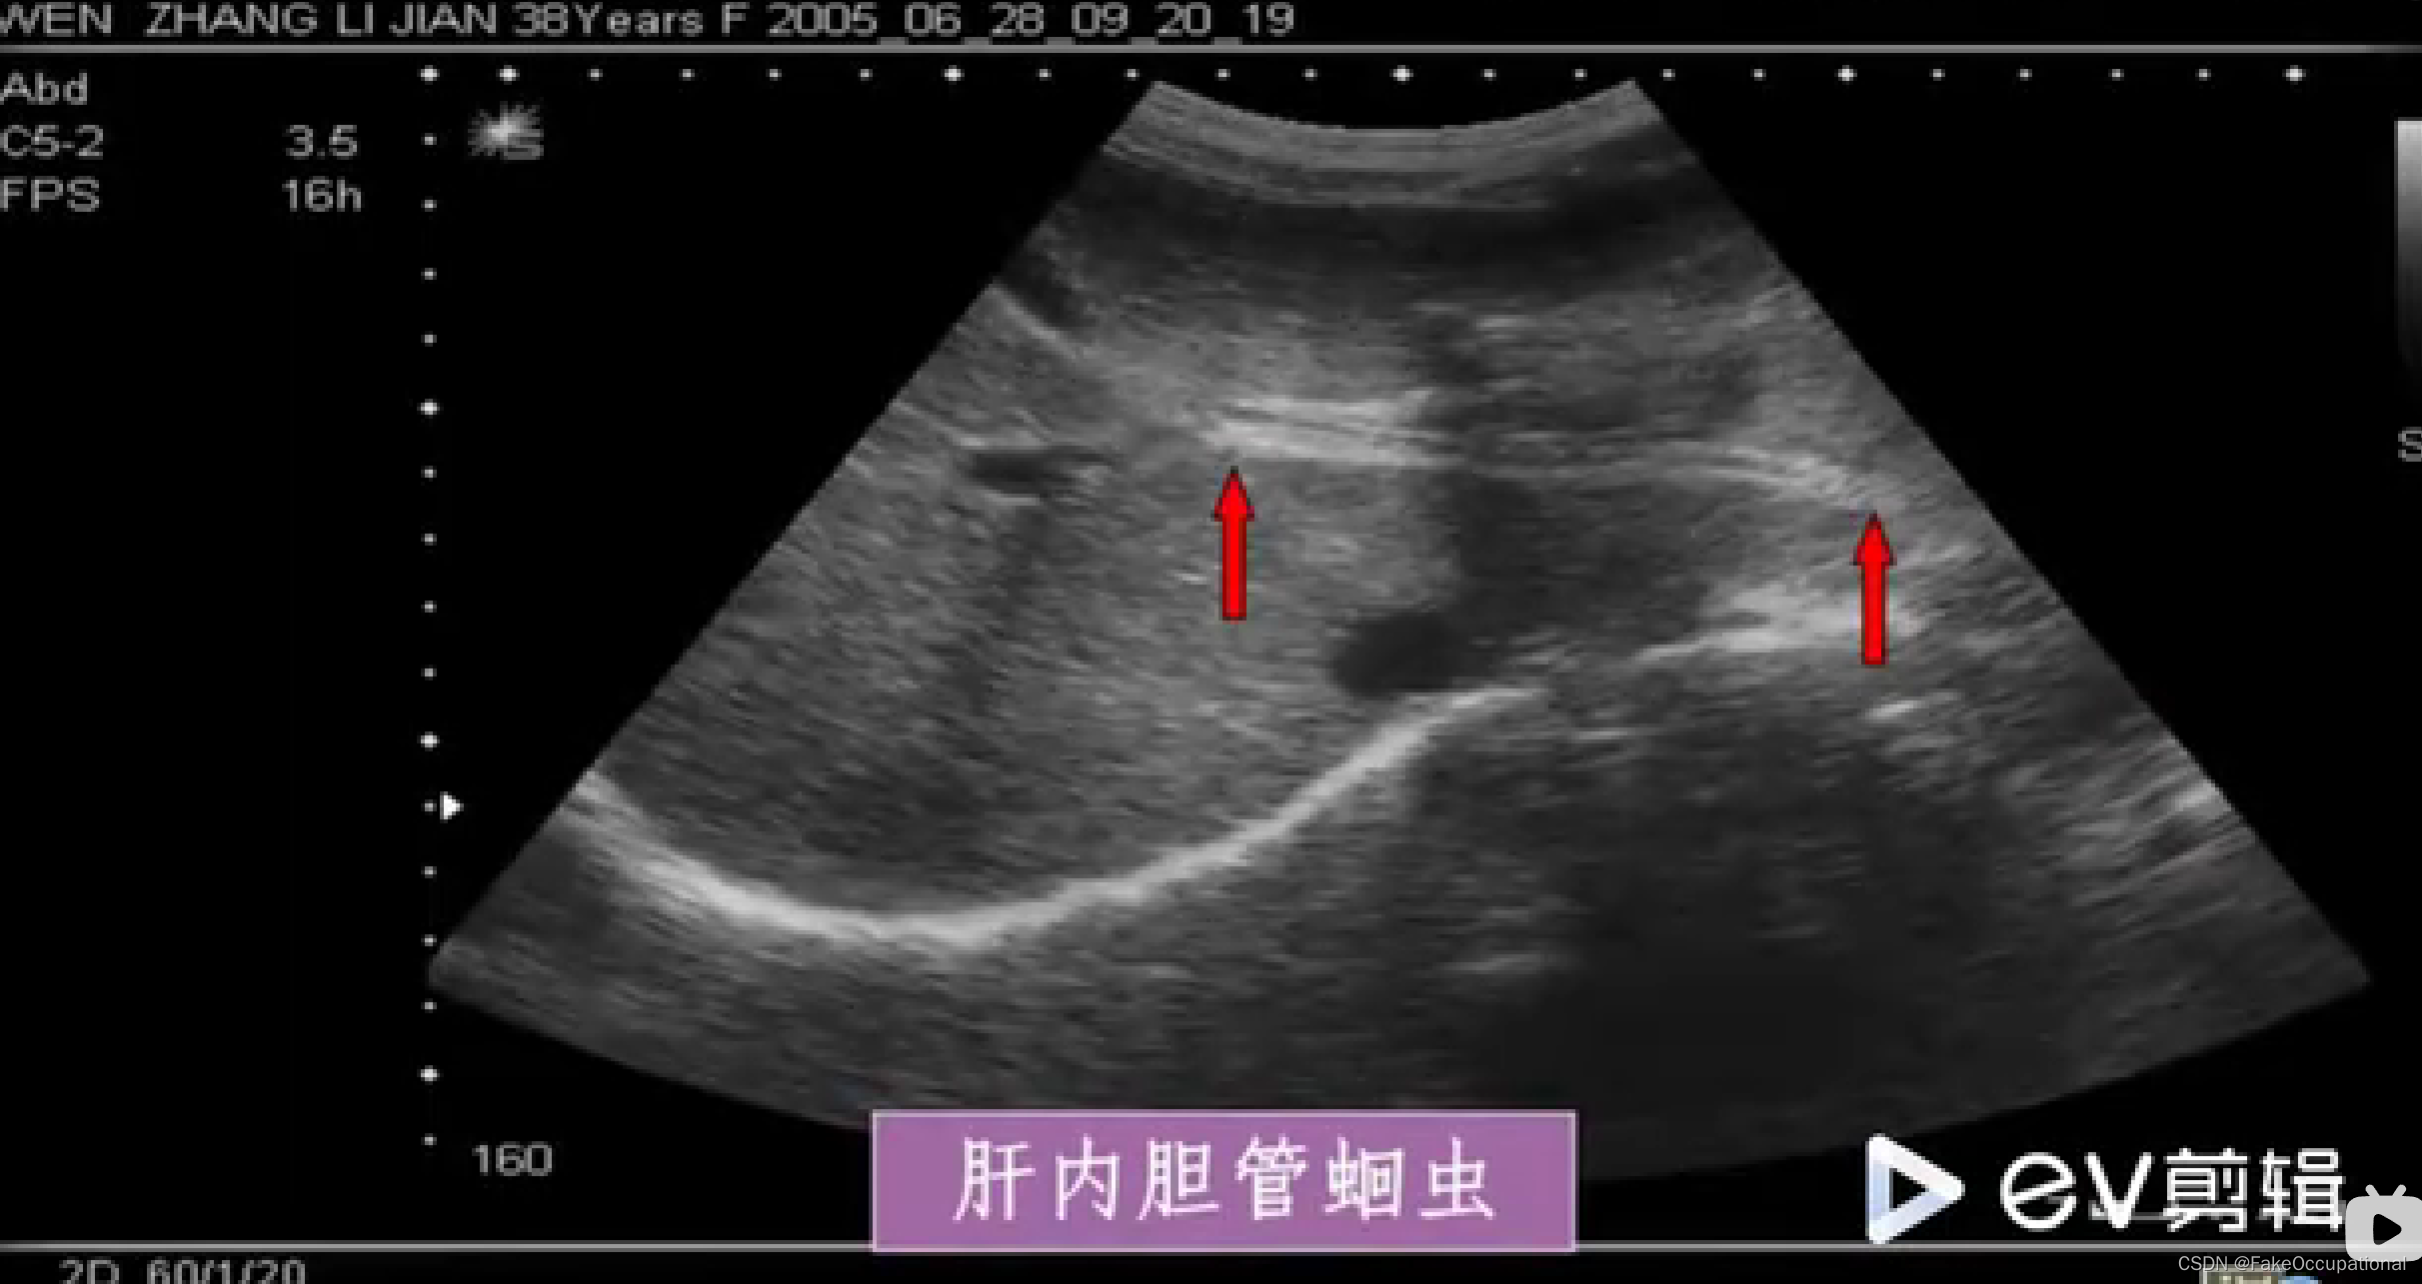

超声声像图: - 肝外胆道不同程度扩张

- 扩张胆管内可见蛔虫回纵切面为双线状长条形的平行高回声带,中央可见暗带;黄切面为“同心圆”状

- 活蛔虫可见其蠕动征象具有特异性诊断意义

- 死蛔虫:虫体萎缩,多节段性光带,中央暗带模糊或消失